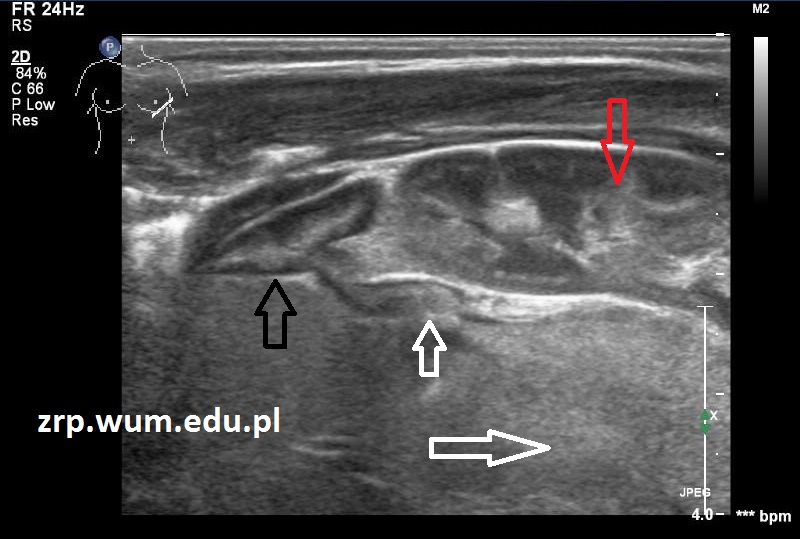

Przypadek 32: Dziewczynka w 1. dobie życia, w badaniu USG po urodzeniu stwierdzono guz wywodzący się z nadnercza lewego oraz liczne ogniska meta w wątrobie.

Rozpoznanie: W badaniu USG uwidoczniono niejednorodny guz ze zwapnieniami, o wym. 47x28mm, wywodzący się z dystalnej części odnogi nadnercza, pozostała część nadnercza prawidłowa. W dalszej diagnostyce potwierdzono neuroblastoma.

(guz - białe strzałki; nadnercze – czarna strzałka; nerka – czerwona strzałka; meta w wątrobie - kilka zmian oznaczono pomarańczowymi strzałkami).